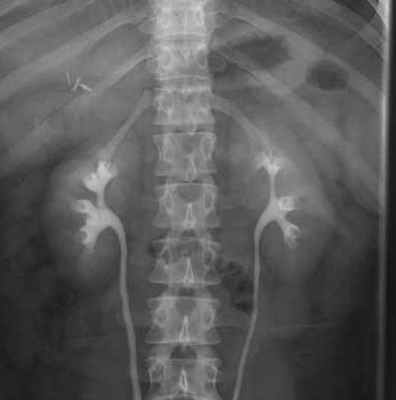

При обычной рентгенографии поясничной области можно видеть контуры нижней половины почек. Для того чтобы увидеть почку целиком, приходится прибегать к введению воздуха в околопочечную клетчатку — pneumoren.

Рентгенологически можно определять скелетотопию почек. При этом XII ребро при саблеобразной форме наслаивается на середину почки, при стилетообразной форме — на ее верхний конец.

Верхние концы почек слегка наклонены медиально, поэтому продолжения длинных осей почек пересекаются над последними на высоте IX—X грудных позвонков.

Почки располагаются по обеим сторонам позвоночника, обычно на уровне ThXII-LIII (справа) и ThXI—LII (слева). В отличие от взрослых у детей, особенно младшего возраста, почки относительно большие, поэтому на рентгенограммах нижние полюса их расположены ближе к гребню подвздошной кости и нередко находятся на уровне последнего. Продольная ось почки расположена параллельно краю поясничной мышцы, так что угол, образованный продольными осями обеих почек, открыт книзу и равен 20—30°, причем у мужчин он обычно несколько больше. Знание этого признака, который легко определяется на рентгенограмме, очень важно, поскольку при патологических состояниях (аномалии развития, пиелонефрит, нефроптоз, паранефрит и т.д.) направление продольной оси почки может меняться с одной или двух сторон.

Нормальные почки дают на рентгенограмме гомогенные бобовидные тени с ровными контурами размером 12x7 см (у мужчин несколько больше, у женщин несколько меньше). Правая почка располагается на 1,5—2 см ниже левой, и тень ее пересекается ХII ребром обычно посредине. У 30% людей обе почки расположены на одинаковом уровне, у 5% людей левая почка расположена ниже правой.

Размеры почек у детей различны в зависимости от их возраста, у новорожденных 4,5x2,7 см, к году эти размеры увеличиваются в 2 раза, а к 13—14 годам — в 7 раз. Почки у детей относительно большие, а поясничная часть позвоночника сравнительно короткая, поэтому на рентгенограммах нижние полюса почек расположены близко к гребню подвздошной кости, а иногда находятся на уровне последнего.

Определение размеров почек имеет большое диагностическое значение при многих заболеваниях (пиелонефрит, опухоль, нефрогенная гипертензия и т.д.). Почки обладают физиологической «дыхательной» подвижностью в пределах тела одного позвонка. Большая подвижность свидетельствует о нефроптозе, отсутствие смешения — о дистопии или поражении околопочечной клетчатки (паранефрит, педункулит).